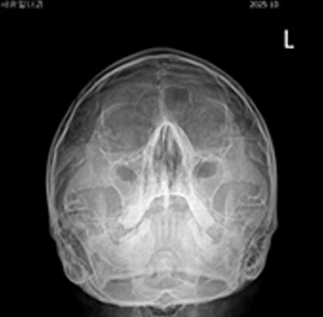

만성기침의 가장 많은 원인인 분비물이 목 뒤로 넘어가는 후비루 증상이 있는 상기도 기침 증후군인데, 비염, 부비동염이 원인인 경우가 많습니다.

후비루 증상은 부비동 엑스레이나 비강 내시경을 통하여 비부비동염 여부를 확인해야 하며, 기침형 천식은 기관지 유발 시험, 호기 산화질소, 객담 호산구 검사 등으로 진단할 수 있습니다. 한편 위식도 역류 질환은 식도로 역류된 위속의 내용물로 인해 불편한 증상이나 합병증이 유발되는 상태를 말하며, 24시간 식도 산도 검사나 위내시경을 통하여 진단할 수 있습니다. 위산이 식도를 넘어 인두와 후두까지 역류하여 점막을 자극하는 경우 후두 내시경을 통하여 인후두 역류 질환을 진단할 수 있습니다.

상기도 기침 증후군 기침형 천식 위산 역류 질환

치료 전 기관지 유발 시험 검사 위식도 역류 질환

img img img

치료 후 기관지 유발 시험 검사 양성 인후두 역류 질환